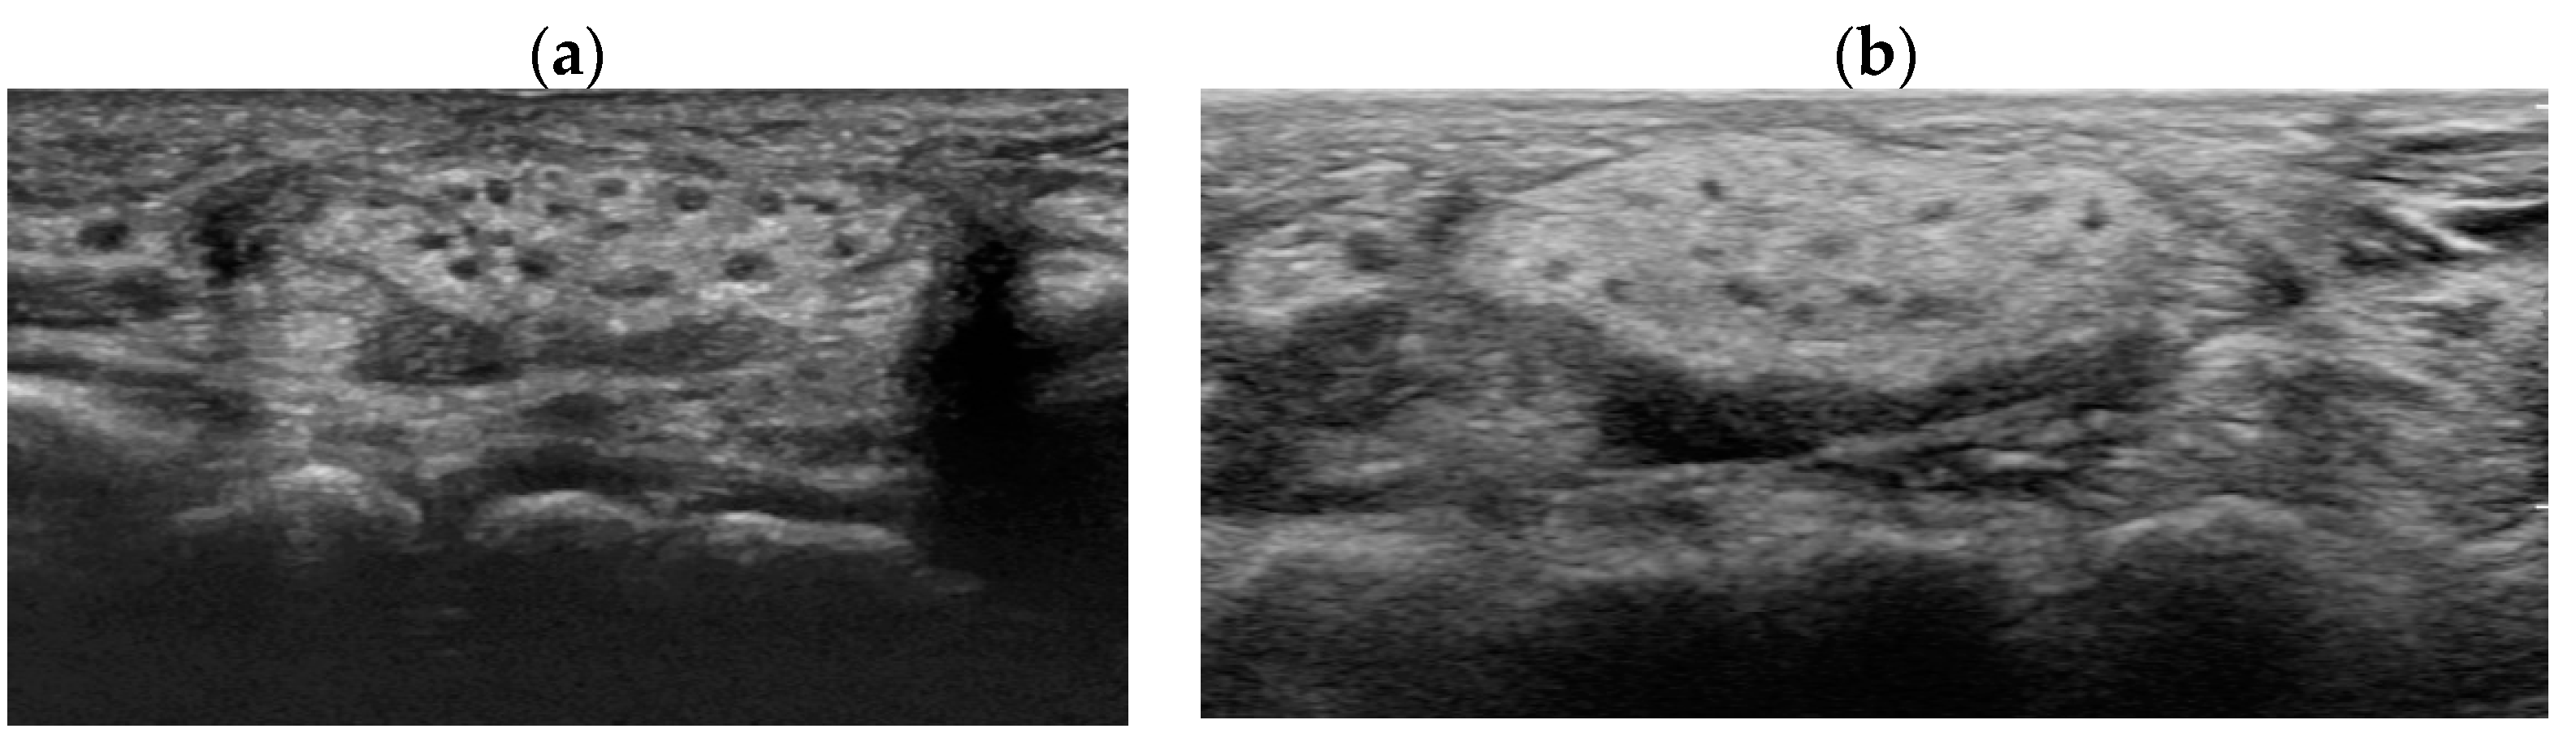

Postoperatively, the patient’s recovery was uneventful without any complications of pain, discomfort, or decreased joint movement. The patient was followed-up annually with the wrist sonographic examination (Figure 6). At the 10th-year follow-up, the patient remained asymptomatic with full opposition function and grip strengths without sensory deficits or further enlargement of the hamartoma in the median nerve, and electromyography and nerve conduction study confirmed no neurologic deficits.

In the diagnosis of LFH, MRI plays a critical role by offering pathognomic radiologic features, low-intensity serpentine nerve fibers embedded in abundant high-intensity adipose and fibrous tissues, also known as “cable-like appearances”.[9] In addition, ultrasonography also serves an essential tool for initial diagnosis and postoperative non-invasive radiologic follow-ups. Ultrasound imaging of LFH is characteristic of the enlarged cross-section of the affected nerve with hypoechoic fascicles embedded in the hyperechoic fibrous and adipose tissues, and recent ultrasonography has shown to provide as equivalent diagnostic evidence as MRIs.[10] While MRIs are beneficial in assessing the extent of the lesion in the initial diagnosis, ultrasonography serves a critical role in serial postoperative follow-ups, as seen in the current case description. However, biopsy and histologic examinations are the only definitive measures for the diagnosis of LFH, which are characteristic of intertwining collagen, fibroblasts, and adipose cells separating nerve fascicles and infiltrating the space between the epineurium and perineurium without inflammation or myelin degeneration.[2]

Figure 6. Ultrasonographic follow-up of left wrist at the postoperative (a) 5th and (b) 10th years.